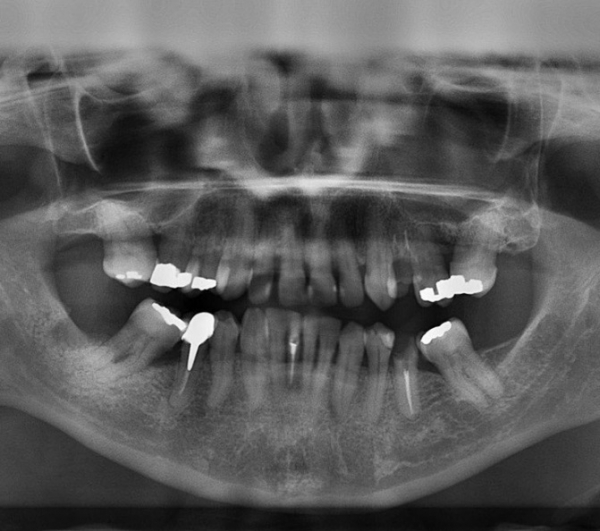

Izpostavljenost organizma živemu srebru že dolgo velja za škodljivo za zdravje ljudi, kar so pokazale že številne raziskave. Živo srebro se med drugim uporablja za zobne zalivke, tako imenovane klasične amalgamske zalivke. Amalgami so zlitine živega srebra in drugih kovin, živo srebro se uporablja zaradi njegovih vezivnih lastnosti in obstojnosti takšnih zalivk.

Raziskava, ki jo je izvedla skupina strokovnjakov z ameriške univerze Georgia, je pokazala, da je raven živega srebra v krvi ljudi, ki imajo v ustih osem amalgamskih zalivk, dvakrat višja kot pri tistih brez zalivk.